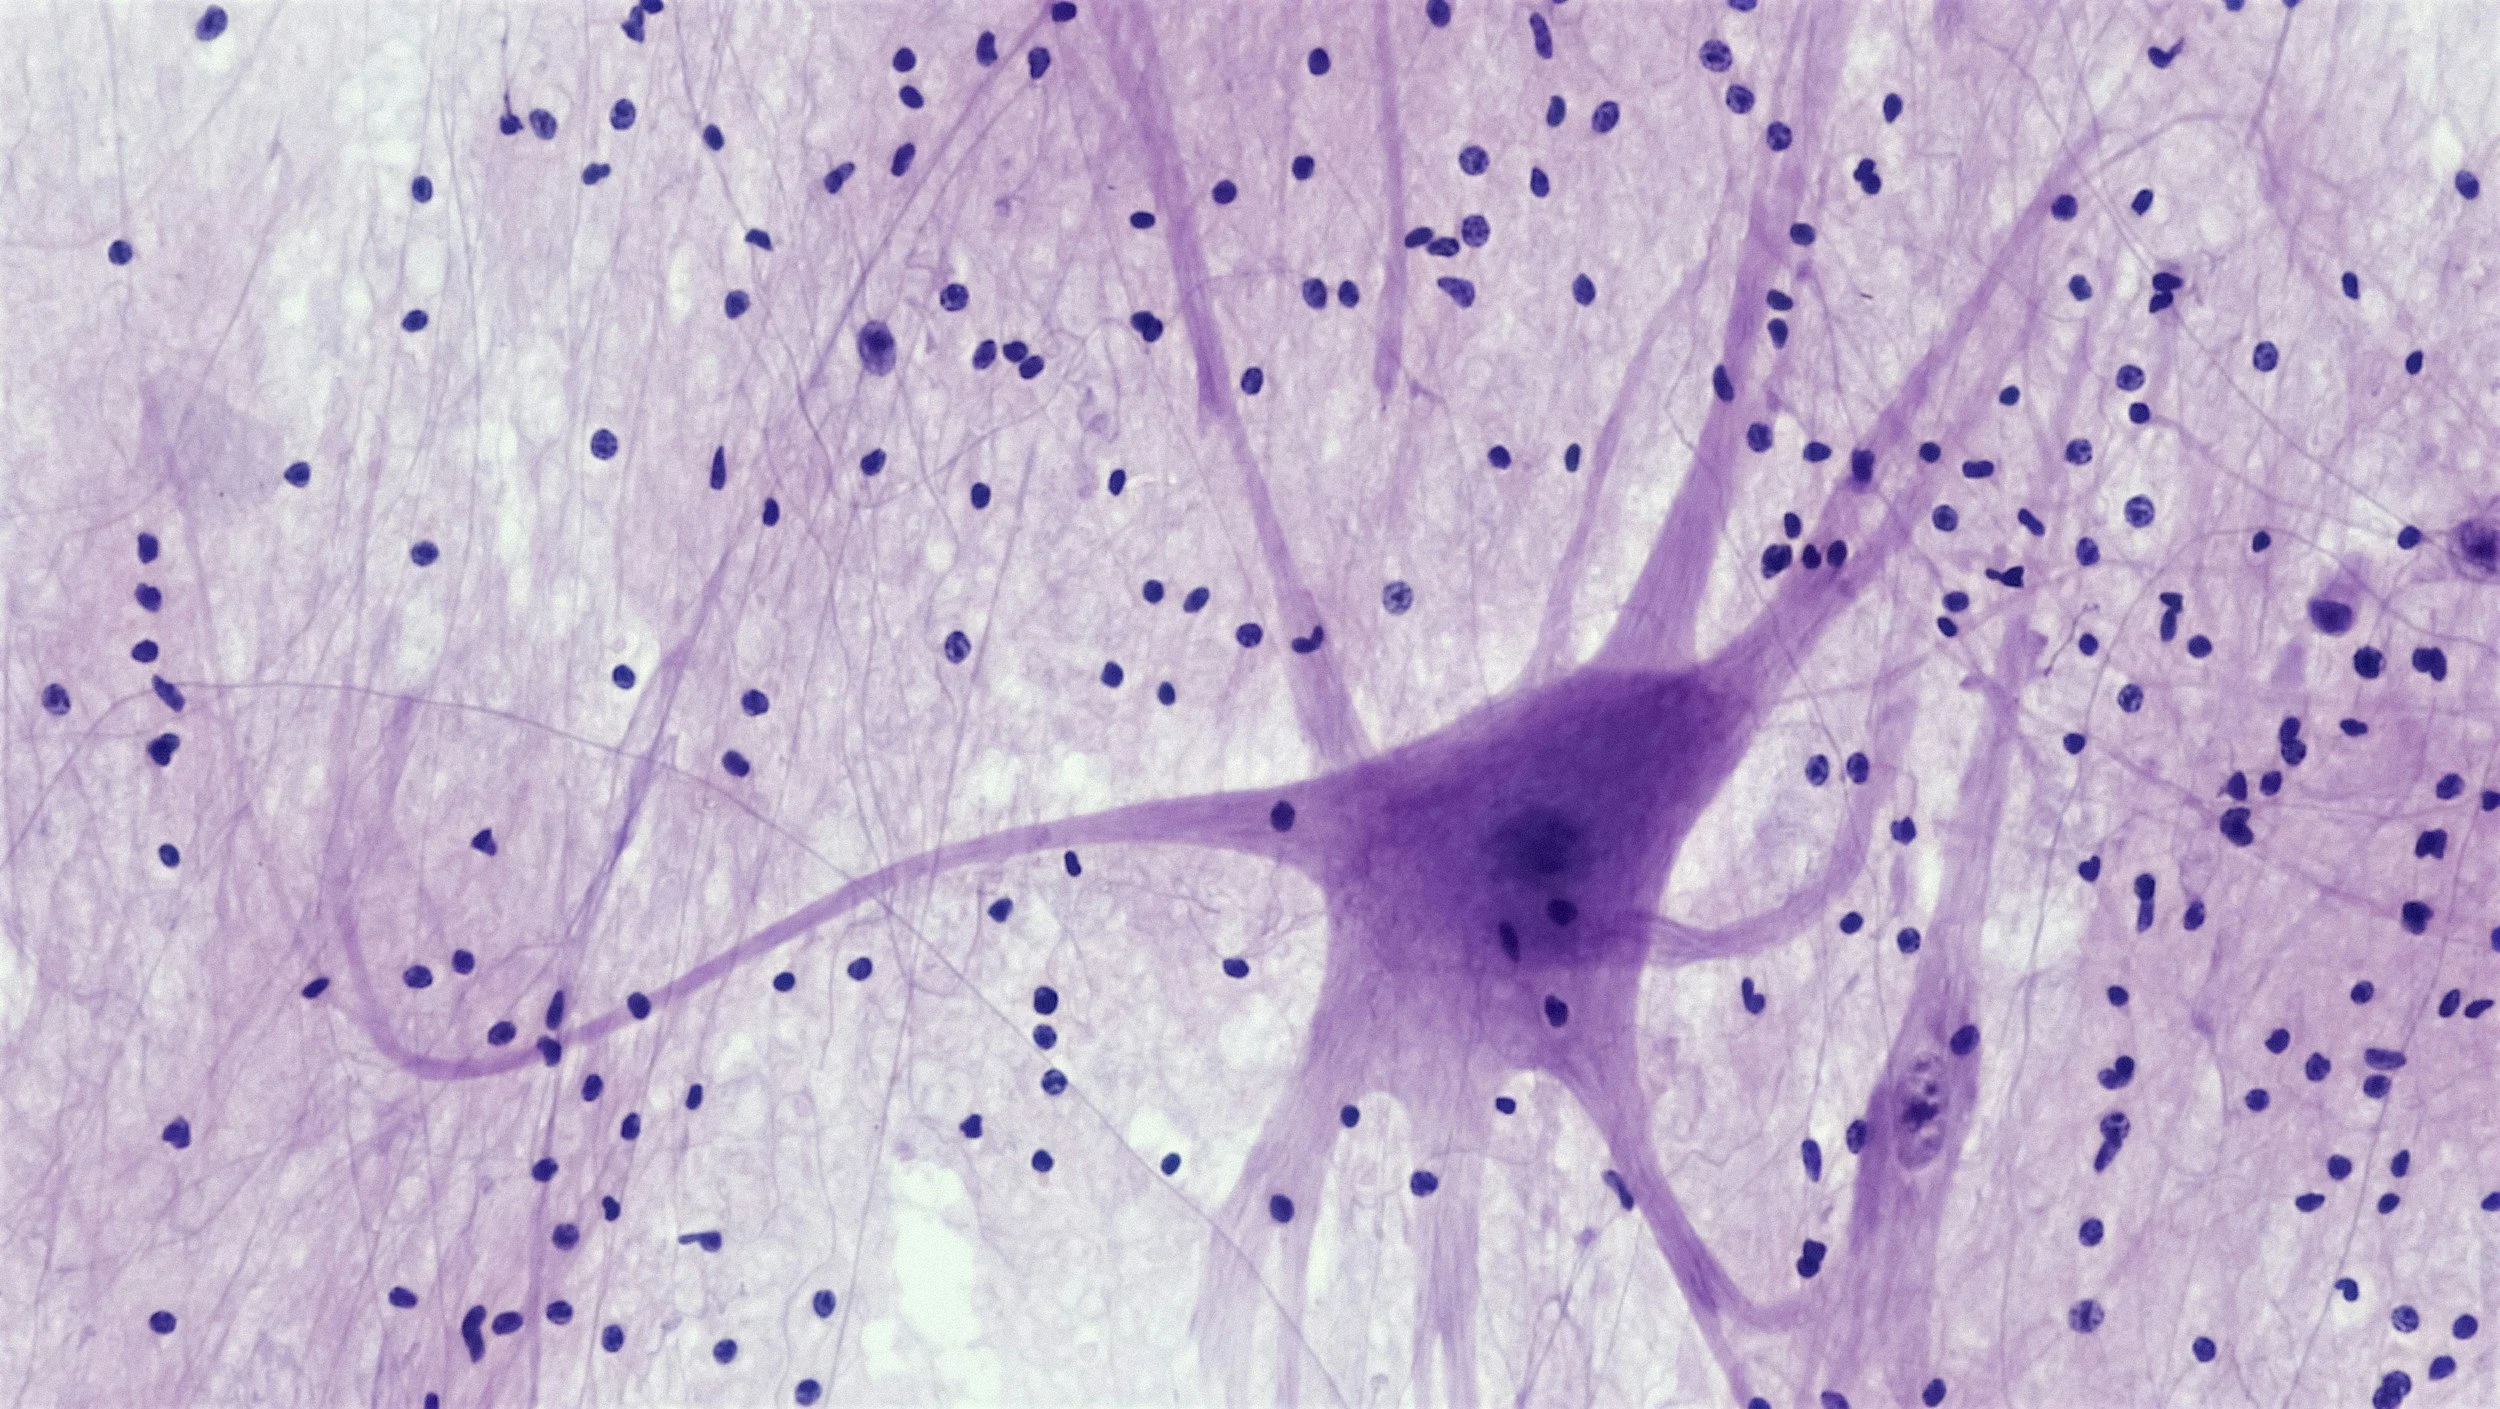

Neuroplasticity is the amazing ability of your brain to rewire itself just by being used differently.

Your brain is made up of billions of nerve cells (neurones) that are connected to each other through pathways.

Similarly, when you repeatedly think or do something, the corresponding neural pathway in your brain becomes stronger and more efficient.

By repeatedly engaging in different ways of thinking, practising new responses, adopting new perspectives and seeking new experiences, you can literally deactivate old neural pathways and strengthen new, more helpful connections.